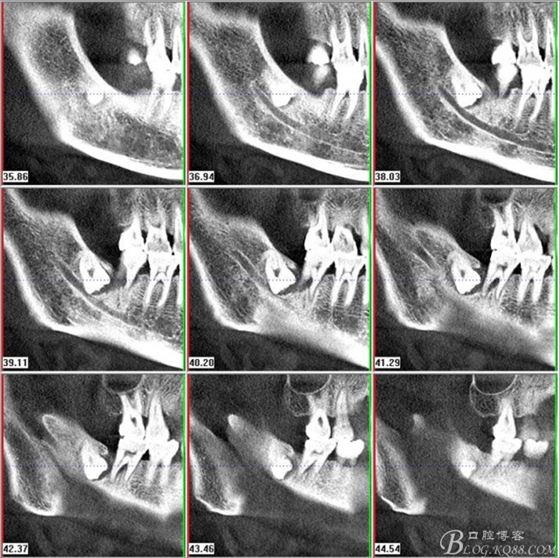

二、術(shù)前CBCT影像:

圖1.47牙冠的近中面緊鄰下頜神經(jīng)管

圖2.判斷47牙根是否吸收

圖3.通過(guò)矢狀面和冠狀面來(lái)判斷48與下頜管及47的關(guān)系

圖4.水平方向48與47之間的關(guān)系

圖5. 48的三維視圖

圖6.測(cè)量48頰、舌側(cè)骨板厚度。

圖7.測(cè)量牙冠近遠(yuǎn)中徑的大小及遠(yuǎn)中骨板的厚度